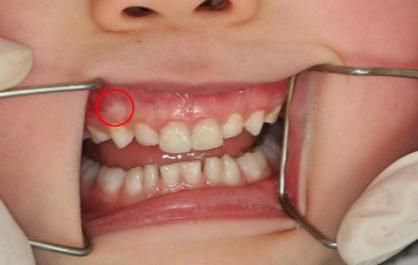

◎ 牙 外 伤

小孩子比较活泼特别是在学龄时期,在玩耍或较剧烈的运动时,常易发生碰撞、跌倒等,比成年人更易发生牙齿外伤。由于孩子处于生长发育时期,牙髓、牙周和牙槽骨组织与成人有一定差别,因此,家长在遇到孩子牙齿外伤时一定要加以重视。根据实际情况,及时带孩子到口腔医院就医的,因为专业的牙科医生会根据孩子牙齿损伤的实际情况给出相应建议以及治疗方法。